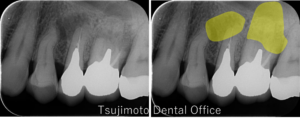

当院では、安易に神経を抜いたり歯を削ったりせず、可能な限り「ご自身の歯」や「歯の神経(歯髄)」を残すことを大切にしています。

マイクロスコープを活用した精密な診断により、他院で「抜歯・抜髄」と言われたケースでも保存できる可能性を丁寧に検討し、適切な処置をご提案します。